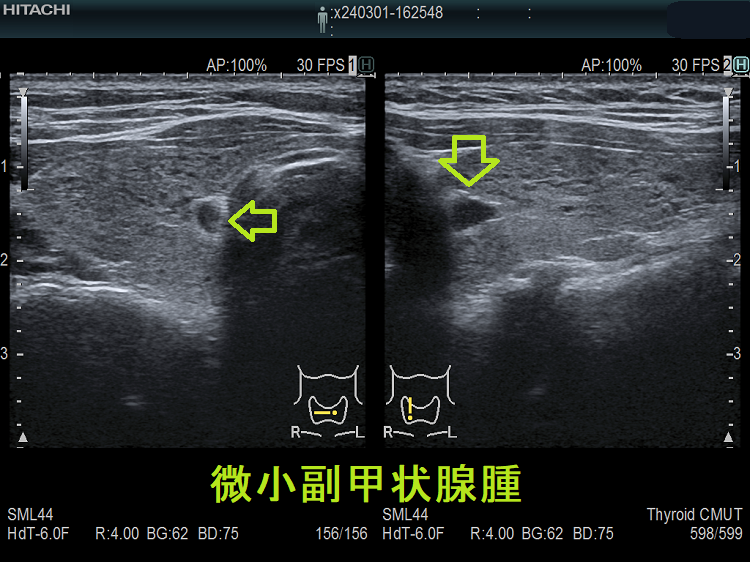

微小副甲状腺腫;血清カルシウムは正常範囲内の上限だが、脱水などの影響で上限を超える場合もある。骨密度は正常で、腎結石(腎臓結石)もない。

血清カルシウム・リン値正常、副甲状腺ホルモン(PTH)濃度も正常の副甲状腺腺腫が存在します。甲状腺超音波(エコー)検査で偶然見つかるケースがほとんどで、さほど大きくないためCT/MRIでは見えない場合が多いです。もちろん、副甲状腺機能亢進していないため治療適応にはなりません。副甲状腺ホルモン(PTH)合成能が低い副甲状腺腺腫ですが、年次フォローするとサイズが増大して、高カルシウム血症・副甲状腺機能亢進症に進展することもあります。[World J Surg. 2017 Jan;41(1):122-128.][Aust N Z J Med. 1998 Apr;28(2):173-8.]

甲状腺内副甲状腺腫は、超音波(エコー)検査で甲状腺腫瘍と形態的に鑑別できない場合があります(実際は下の写真のように診断できていますが・・)。特徴的な超音波(エコー)所見は、腹側の高エコーで感度86%、特異度100%です[Surgery. 2012 Dec;152(6):1193-200.]。さらに、99m-Tc MIBIシンチグラフィーで取り込み(集積)があれば甲状腺内副甲状腺腫と診断できます。